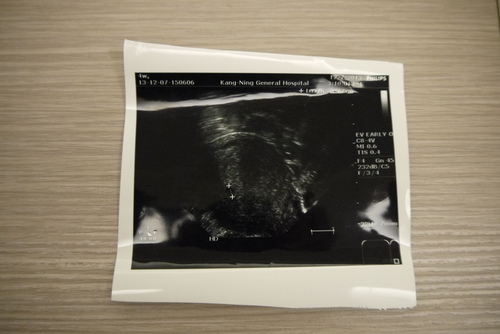

11/30 4WEEK 康寧醫院初診-尹長生

醫生用腹超照不到,說還太小要我下周再來,沒有用陰超確認

12/7 5WEEK 康寧醫院複診-尹長生

醫生用腹超依然照不到,改用陰超,照到小黑點,醫生判斷為4周大小,要我2周後回診

但我非常擔心,因為依照行房日期計算,應該要有5周大小

上週並沒有用陰超確認,不知道現在的大小是有長大還是沒有長大,非常擔心